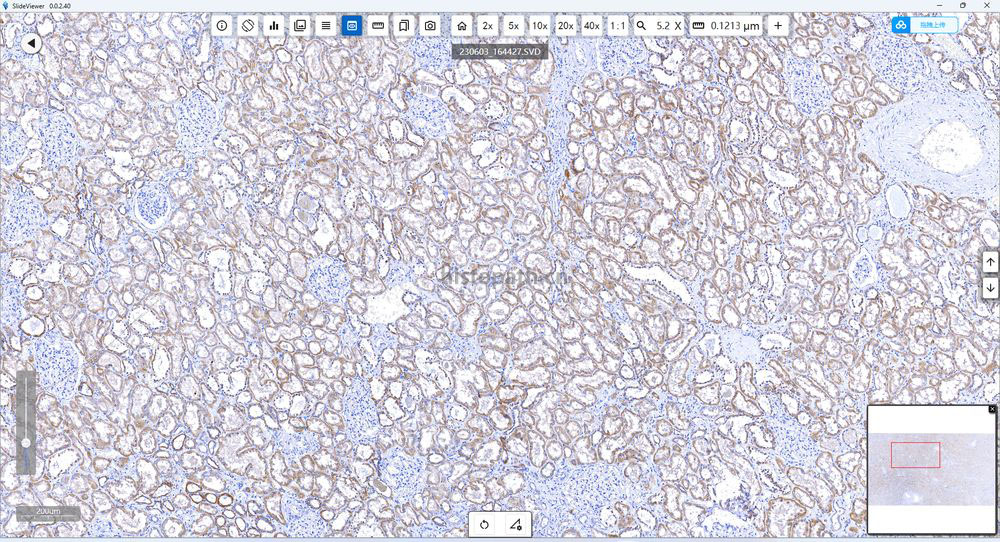

免疫组化:

是应用免疫学基本原理——抗原抗体反应,即抗原与抗体特异性结合的原理,通过化学反应使标记抗体的显色剂(荧光素、酶、金属离子、同位素)显色来确定组织细胞内抗原(多肽和蛋白质),对其进行定位、定性及定量的研究,称为免疫组织化学技术(immunohistochemistry)或免疫细胞化学技术(immunocytochemistry)。

结果:阳性部位棕褐色,细胞核天蓝色,对比鲜明,无背景着色。